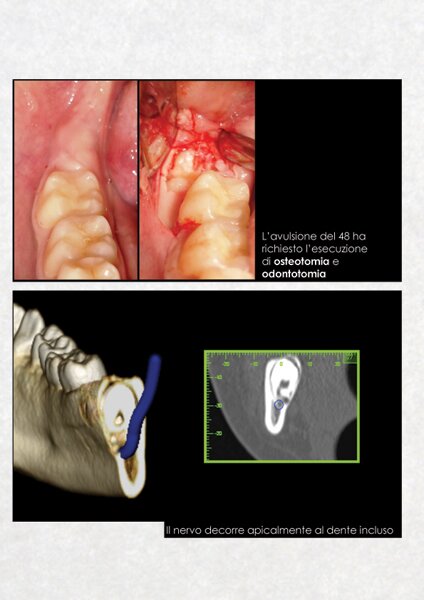

La diagnostica dei casi complessi di chirurgia orale ed implantologia è realizzata, a partire da una TAC dentale a cui si sottopone il paziente, mediante l'utilizzo del software computerizzato ONE SCAN 3D. Attraverso questo programma è possibile ottenere una ricostruzione tridimensionale del mascellare/mandibola del paziente, identificare le strutture anatomiche di riferimento, valutare i tessuti duri e molli, pianificare l'inserimento degli impianti nell'osso disponibile e ottenere un valido consenso informato del paziente all'intervento chirurgico.

Questo approccio moderno e tecnologico consente all'odontoiatra di lavorare con la massima serenità,riducendo al minimo qualsiasi imprevisto in fase operatoria.